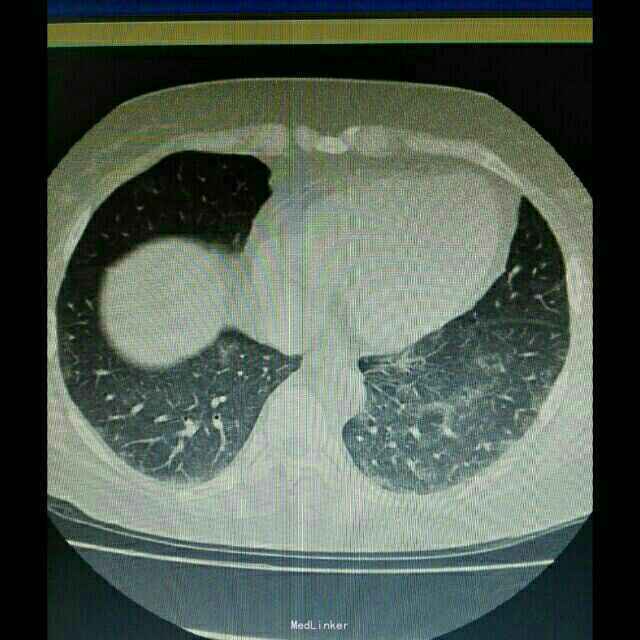

辅助检查:入院后行紧急胸部CT检查提示双肺弥漫性炎症改变,双下肺更加明显。

诊断:肺部感染,异体肾移植状态 治疗:根据胸部CT检查提示,真菌感染可能性大,给予科赛斯抗真菌治疗,加用舒普深抗细菌治疗。进一步检查生化、降钙素原、真菌D葡聚糖等炎性指标,监测患者体温、血气等指标。